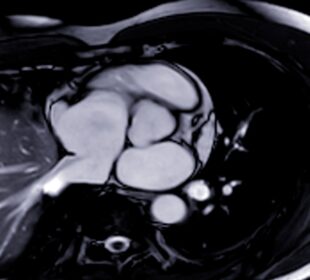

Nauja viso kūno magnetinio rezonanso tomografijos (MRT) paslauga sulaukia vis daugiau dėmesio dėl galimybės aptikti vėžį anksčiau nei pasireiškia simptomai. Viena tokių ...12 sveikų užkandžių idėjų nėštumo metu